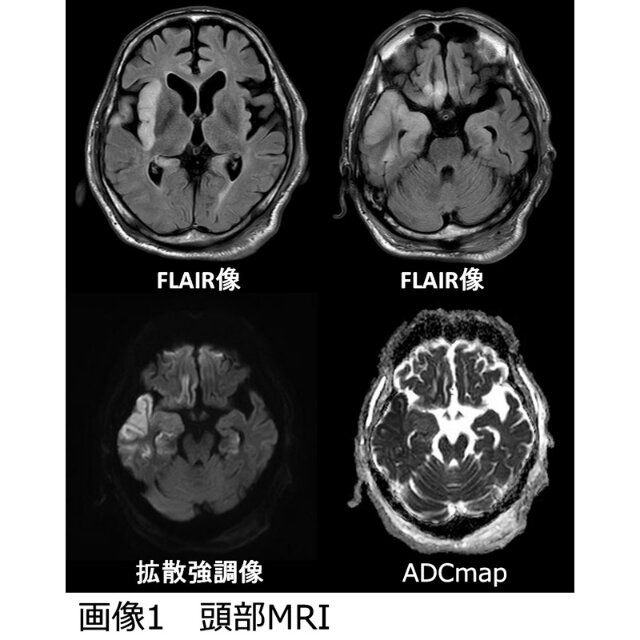

· 単純ヘルペス脳炎は成人における散発性の急性ウイルス性脳炎の中で最も頻度が高く,起因ウイルスが判明 MRI所見として,T1強調画像にて等~低信号,T2強調画像とFLAIR画像にて高信号を示すことが多く,病初期では拡散強調画像(diffusion weighted imaging:DWI)が有用なこともあり,MRI検査ではT1単純ヘルペス脳炎の画像所見の特徴を教えてください 1年を通して非流行性の脳炎としては最も高頻度に発生する急性脳炎で,新 生児,年長児,成人と,どのような人でも感染発症の可能性はあります。感 染病原体には単純ヘルペスウイルスtype1(HSV1)とtype2(HSV2)があ ります。成人の単純単純 ヘルペス 脳炎 はMRIで異常所見 を検出 する 頻度 が高く, 病変 は側頭葉 にびまん 性,島病変 を伴いやすいのが 特徴 である. 一方,自己免疫性脳炎 では 内 側側頭葉 に限局 し, 基底核病変 を伴うことが 多いことが 鑑別点 である17). 膠原病 に合併 する 脳炎 では, 全身性 エリテマトーデ ス(CNS ループス), Sjögren 症候群,再 発性多発骨軟骨炎18

りみられず。頭部MRIでADEMが疑われ、加療中。h243 加療中 不明 接種4日後、痙攣重積、入院。 情報不足 発症がやや早い 12 h2310 5~ 10歳 微研jr103 脳炎 接種翌日、発熱。接種7日後、けいれん重積。急性脳症にて入 院。入院翌日、icu入室し、全身麻酔管理。重積頭部 MRI 単純 ヘルペス 脳炎 が疑われた 患者 において 頭部 MRI検査 は強く推奨 され, 可及的速 やかに 行われるべき 検査 である. 水平断 T1 ,T2 ,diffusionweighted MRI image(DWI), T2 fluid attenuated inversion recovery(FLAIR )を施行 することが 望ましい. 4.ICUではすぐにMRIというわけにいかないケースも多々あるので、ヘルペス脳炎疑いの時は頭部CTをしっかり確認する必要がありそうです。 治療については、ヘルペス脳炎を疑えば 確定診断の前に アシクロビル点滴投与です。成人は10mg/kg静注(高齢者では75mg/kg)、1日3回、21日間です。この際、生食250mlで溶き、2時間かけて投与することが重要です。小児や新生児などは